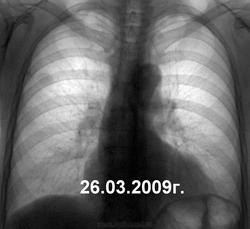

Очередная динамика. На 1-м снимке - на тенюшку не обратили внимания, на 2-м - отправили в онко, был 3-й, но к сожалению потерян в дебрях компьютерной памяти. Со слов пациентки - состоит на учете в тубдиспансере. Может и вылечат?

Мытарства в медицине конституционно бесплатной, а фактически финансово неподъемной для большинства больных выглядят по типу ни в сказке сказать, ни пером описать. Я же честно написал, что на первом снимке - стоит норма, поставленная мною. Но на втором - уже консультация онко. Каким образом пациент оказался на учете в ПТД - одному богу известно. И опять же вопрос, что нужно было делать во-время 1-го снимка, как позиционировать, идентифицировать ту тень?

По характеру развития-онкопроцесс.Игорь Иванович, на первом снимке уже патология.При ретроспективе хорошо видно.Опухоль и к тому-же первичная.Росла ,росла и доросла до мезотелиомы.